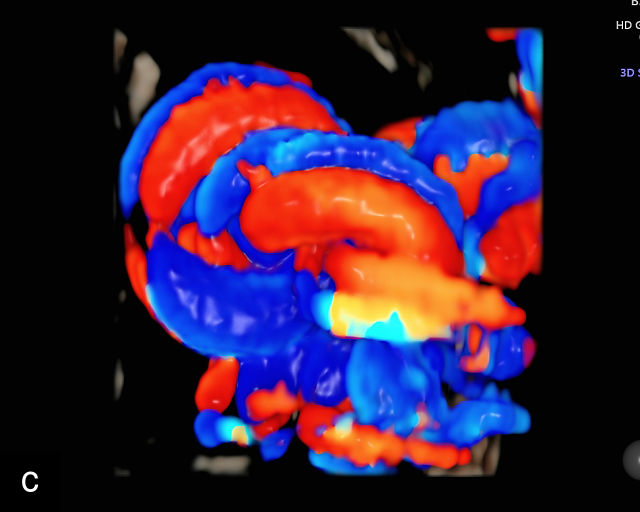

Placental chorioangiomas

Chorioangiomas are benign tumors of the placenta, arising from chorionic tissue.141 These tumors consist of capillaries and cellular stroma in varying proportions.141,142 While clinical diagnosis of chorioangiomas is relatively uncommon, histopathological analysis reveals their presence in approximately 1% of all placentas.142 Most chorioangiomas identified on prenatal ultrasound are incidental findings during routine examination and are typically those that are larger in size.9 Consequently, the prevalence of chorioangiomas detected sonographically is significantly lower than the prevalence observed in pathological examinations of placentas. More rarely, chorioangiomas may be detected during ultrasound evaluation for polyhydramnios or FGR.143 Large chorioangiomas (greater than 4 cm in diameter) are thought to occur in approximately 1 : 3500–1 : 9000 pregnancies (0.01–0.03%).141 These larger chorioangiomas may be associated with significant complications, including polyhydramnios, fetal hydrops, fetal anemia, FGR and even fetal death.9,141,143,144,145 A systematic review reported a fetal death rate of 8.2% in cases of prenatally diagnosed chorioangioma in which no intervention was performed.145 Additionally, preterm birth before 37 weeks occurred in 34.1% of these pregnancies (95% CI, 21.1–48.3%). The study also found that 24.0% of infants (95% CI, 13.5–36.5%) were born small-for-gestational age.145 The most important predictor of outcomes was the size of the tumor.145

The typical sonographic appearance of a chorioangioma on grayscale ultrasound is a well-circumscribed mass arising from the fetal surface of the placenta, protruding into the amniotic cavity, and distinctly separate from the placenta (Figure 12; Video 7). These tumors are most commonly located near the umbilical cord insertion site on the placenta. Sonographically, they may appear hypoechoic or hyperechoic and are often heterogeneous, with possible calcifications, hemorrhage or infarction visible within the mass.9 The appearance of these masses may change over time.141 Color flow Doppler imaging typically reveals vascularity within the tumor, showing low-resistance vessels and arteriovenous shunts (Figure 12c–e; Video 7).9 These shunts are believed to contribute to fetal complications such as high-output cardiac failure, anemia and hydrops.141 Three-dimensional ultrasound may be helpful in assessment of the mass.146 Importantly, the differential diagnosis includes placental hemorrhage, and color flow Doppler is essential to assist in making the diagnosis.

12

Grayscale (a,b), color Doppler (c,e) and power Doppler (d) images of chorioangiomas, showing heterogeneous masses protruding from the placental surface.

7

(a–c) Color flow and power Doppler imaging of placental chorioangiomas.

When a chorioangioma is identified on prenatal ultrasound, close fetal surveillance is essential. Initial monitoring includes weekly ultrasound examinations to assess amniotic fluid volume and fetal cardiac function, as polyhydramnios and hydrops can develop rapidly. Polyhydramnios is the most common complication of chorioangioma, complicating between 14% and 28% of cases, and when severe, may lead to maternal discomfort, respiratory embarrassment and preterm labor.141,143,147,148 Fetal growth should be evaluated every 4 weeks. Maternal mirror syndrome, with severe pre-eclampsia has also been described.149,150

Management of complications related to chorioangioma may include interventions such as amnioreduction to manage severe polyhydramnios.149,151 More recently, a variety of fetal surgical procedures have been developed to treat these tumors, with varying degrees of success. Additional interventions include intrauterine fetal transfusion to correct anemia and various fetoscopic techniques to occlude tumor vessels, such as embolization with injection of vascular plugs, and radiofrequency or laser ablation of the feeding vessels.143,144,152,153,154,155,156,157